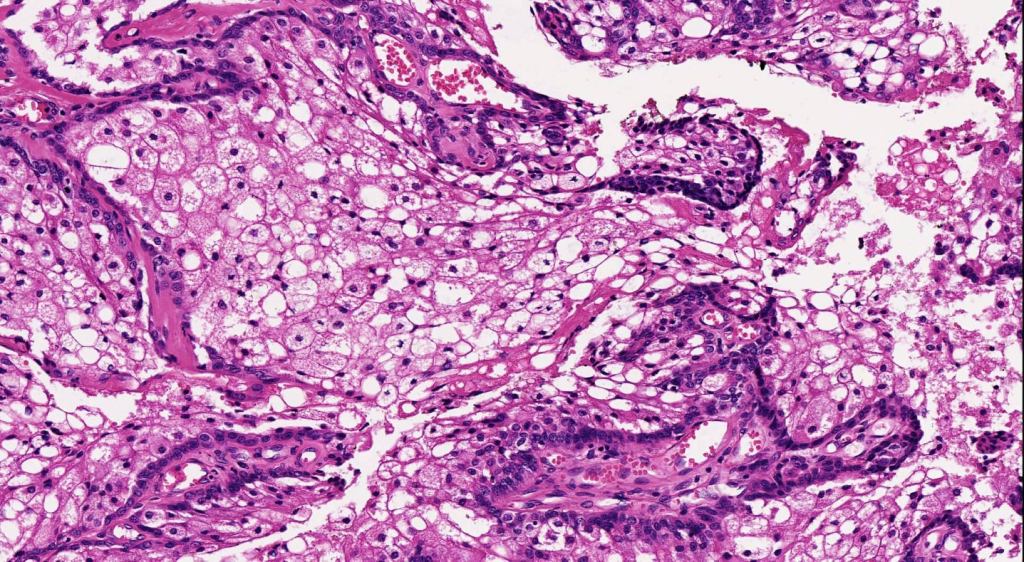

•Random distribution of basaloid cells & sebocytes (<50% sebocytes)

•Duct formation, often with holocrine secretion generally present

. CAM5.2, keratin 14, adipophilin, EMA +ve, BerEP4 negative (compare with BCC- EMA -ve, BEREP4 +ve)